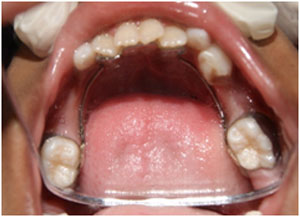

Space maintainers are intra oral appliances (spacers) which prevent teeth from tipping and moving into an extraction area. Space maintainers work by keeping the space open so that adult replacement teeth will be able to erupt into the mouth in the correct location.

Children often need space maintainers after they have had a primary (baby) tooth extracted. A space maintainer can be either cemented to one or more remaining teeth or it can be removable appliance. The space maintainer will need to stay in place until the succedaneous tooth erupts into the extraction area. Space maintainer need to be checked by a dentist twice a year and adjusted if necessary. After the extraction of primary posterior tooth, the adjacent teeth will often move into the extraction space. This unwanted movement of adjacent teeth leads to a loss of space- space that will needed in the future by the succedaneous (adult) teeth.

If extraction space is allowed to close up, the future adult tooth will not able to erupt into mouth correctly. If teeth are allowed to tip into an extraction area, the unerupted future adult tooth may end up being impacted (stuck). Space loss often leads to an adult dentition that is crowded and a child with this problem will need orthodontic treatment later on to correct it.

Space maintainer can also be used as preventive orthodontic appliance. In cases involving moderate crowding in the mixed dentition (6-12 yrs), a LLA (Lower Lingual Arch) space maintainer may be used to prevent unwanted shifting of permanent lower molars.